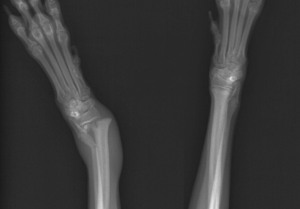

犬の成長板骨折 犬の成長板骨折とは 成長板骨折の実際の症例 犬の成長板骨折とは骨には成長板というものが存在します。成長板は成長期に骨を伸ばすために働く軟骨のことですね。この成長板は成長期にしか存在せず、成長期が終わると骨に置き換わ...